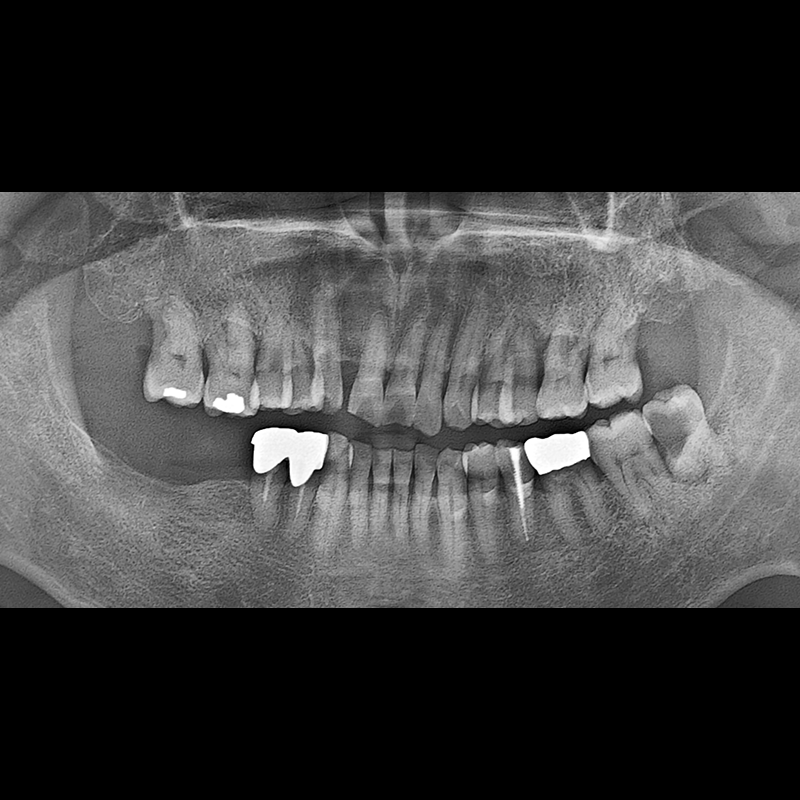

IMPLANT

BEFORE AFTER